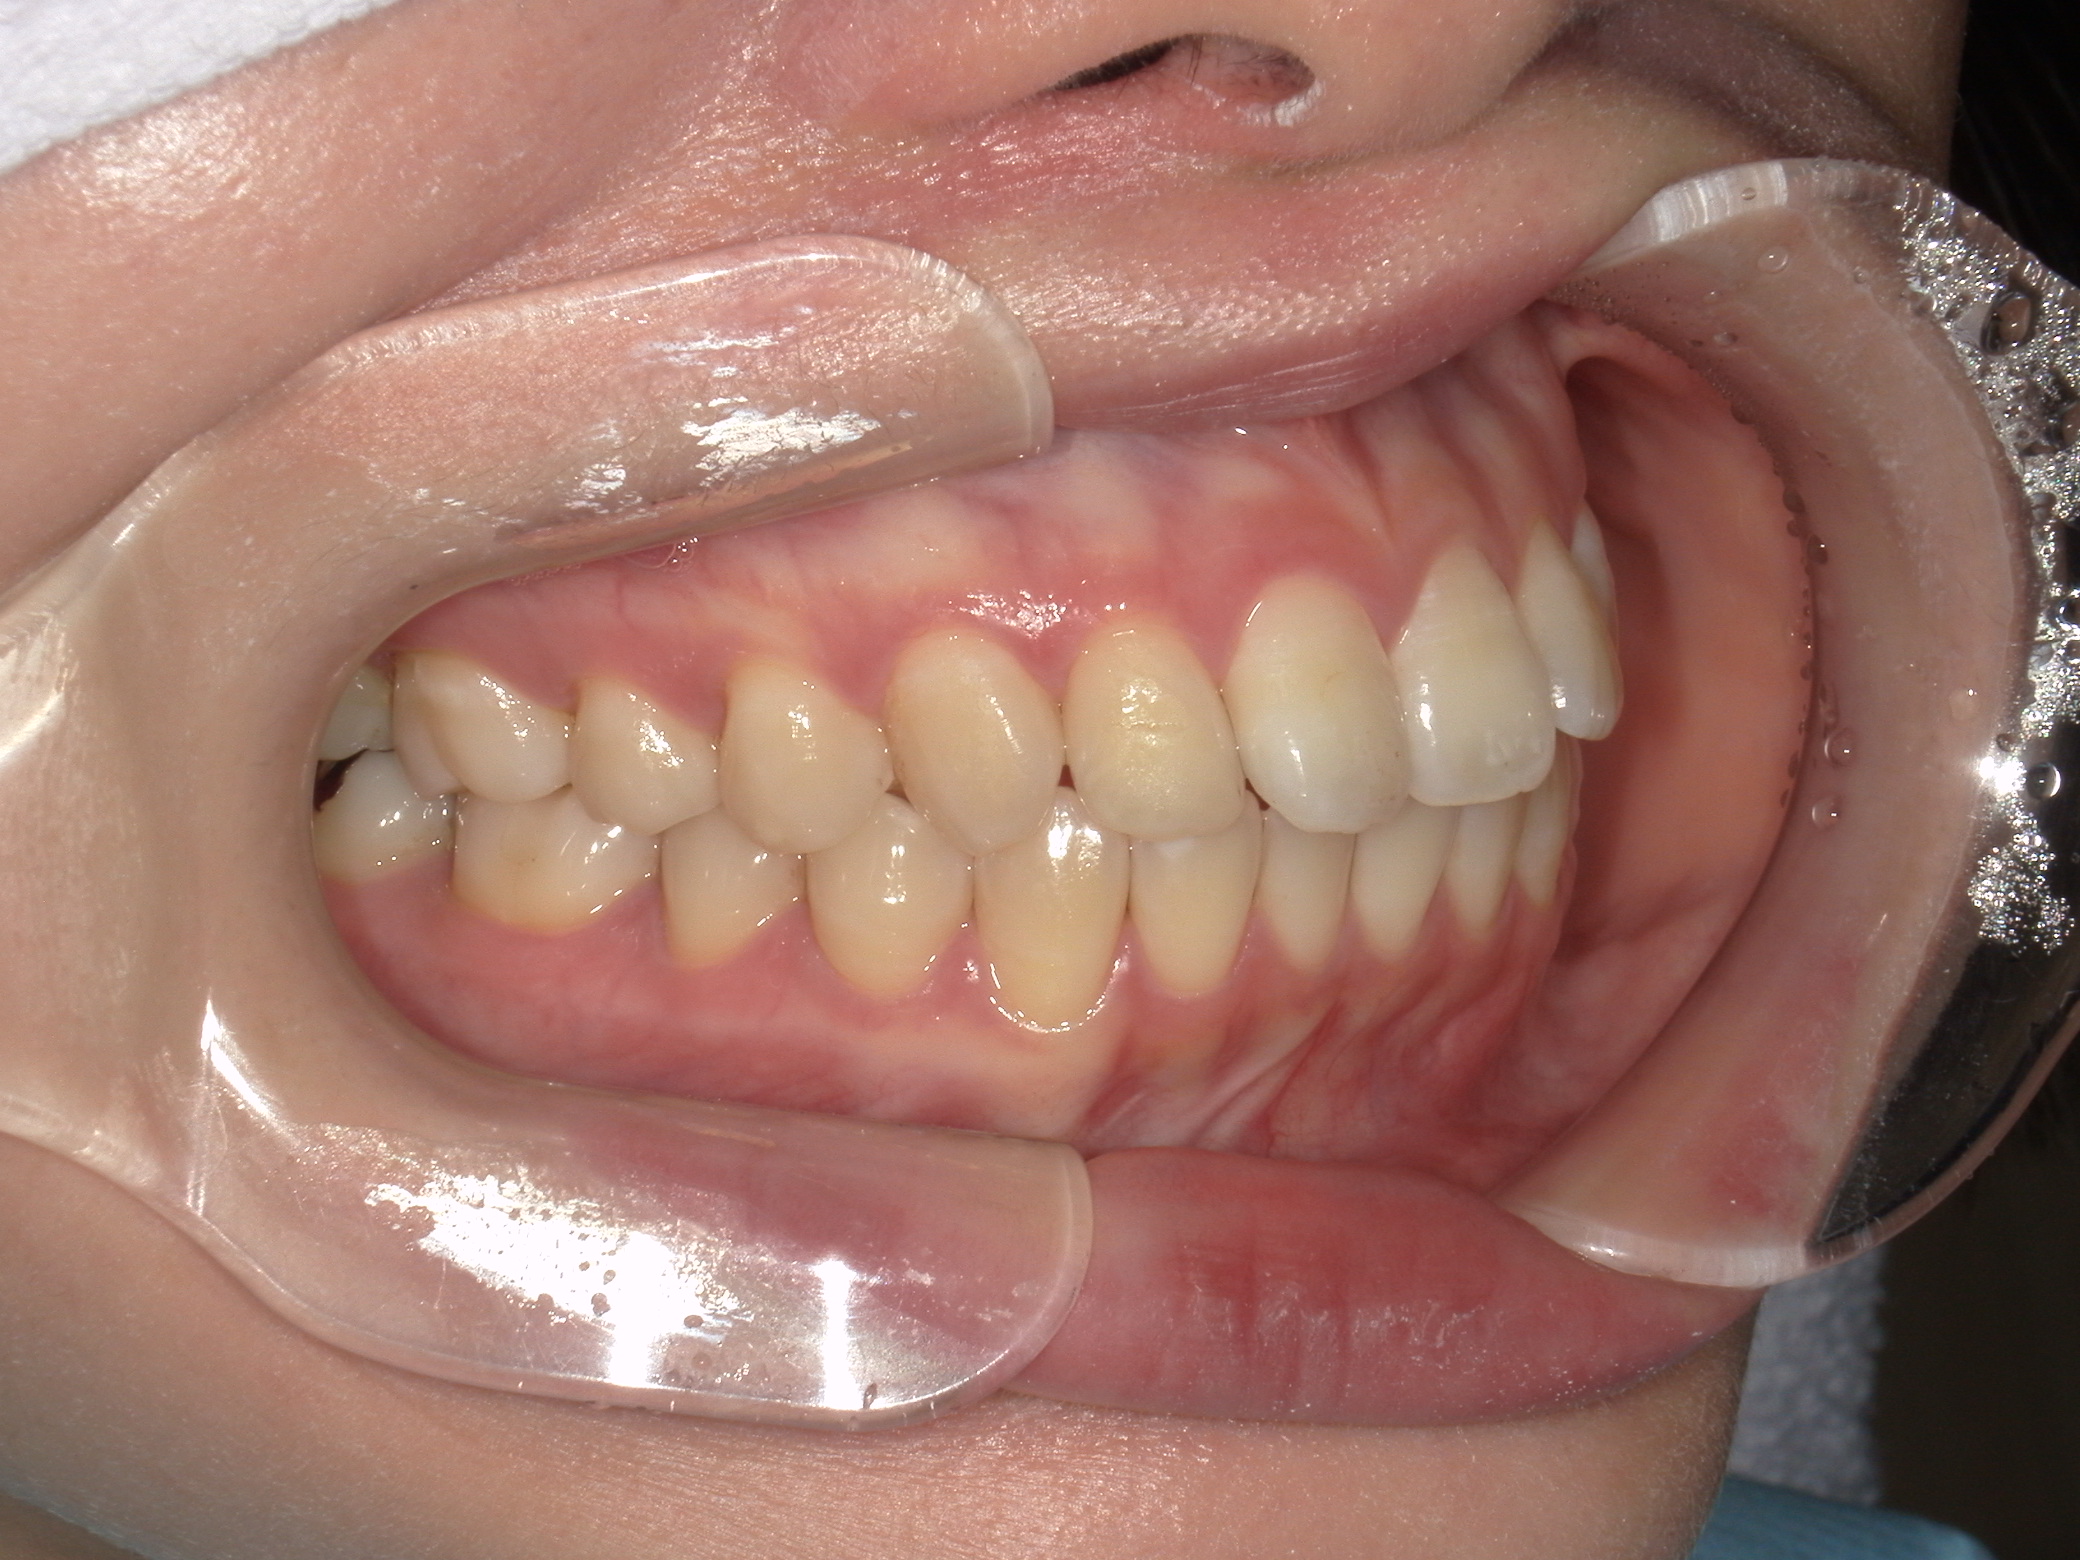

ご相談内容・お悩み

口元の突出感

口元の突出を主訴に来院。

上下小臼歯抜歯により突出感を改善する計画を立てた。確立した咬合を崩さないように治療を進める事を目標とした。

患者はハーフリンガル矯正を希望した。

治療後、口元の突出感の改善、咬合関係は維持することができた。